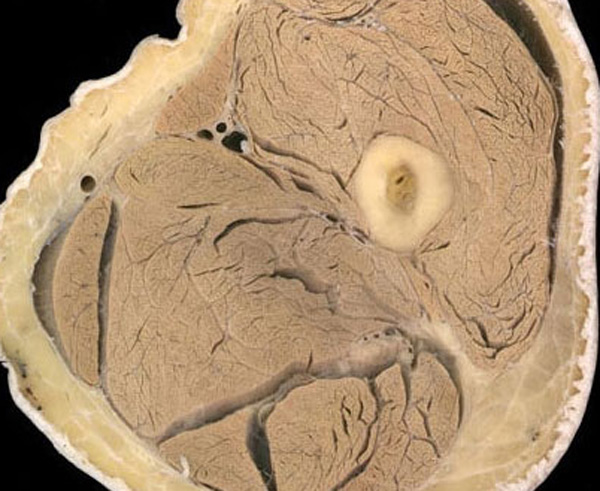

女性生殖器官医学切片(3)

女性生殖器官医学切片